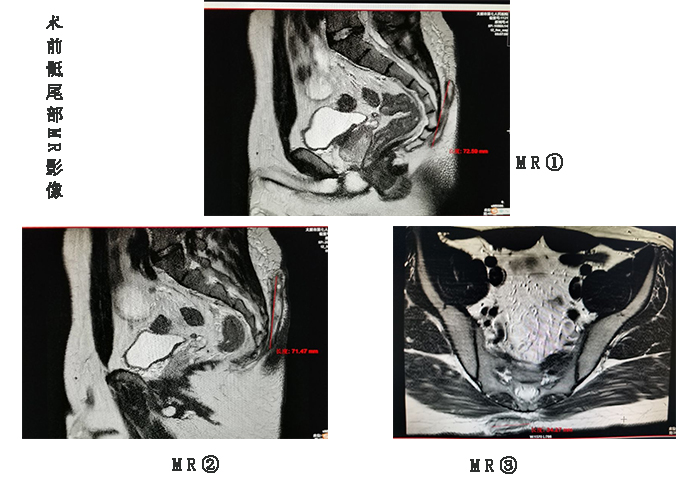

在完善一系列术前相关化验检查后,翟主任组织团队分析了患者的病情,从MRI的结果来看,病灶的范围比预想的还要严重,思忖片刻,翟主任拟定完整切除骶尾部感染灶,同时请二人麻将指南网 烧伤整形外科雷晋主任会诊,决定行骶尾部创面带蒂轴型皮瓣转移术,努力做到一期愈合。